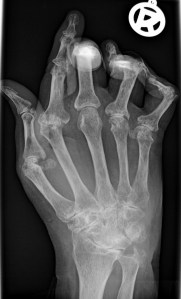

Since it’s initial approval for use in NHL, rituximab has been used to successfully treat advanced rheumatoid arthritis and has also been part of anti-rejection treatments for kidney transplants (both involve B cells. Then news came last week that it could even slow the progression of rheumatoid arthritis (RA) in the early stages of the disease.

The B-cells mutated in NHL and involved in RA are part of the human immune system and are responsible for making antibodies against ‘foreign invaders’. Mature forms of B-cells have a protein called CD20 on their surface.

This month’s exciting study by Professor Paul-Peter Tak from the University of Amsterdam showed that rituximab in combination with the drug methotrexate could slow the progression of early stage rheumatoid arthritis (RA).

The study involved 755 patients diagnosed with RA within the last year. Methotrexate is already considered to be the best treatment for these patients and 12.5% of the patients taking only methotrexate in this study experienced significant reduction of their symptoms. However, compare this to the 30.5% of patients taking a combination of methotrexate and rituximab, and it is clear that rituximab is effective. Issues of cost have been raised in relation to rituximab, but if it turns out to be as effective in treating early RA as this study suggests, then it may ultimately save the health services and insurance companies money as slowing or stopping the progression of the disease will result in fewer patients needing the more expensive treatment and care required in advanced RA.